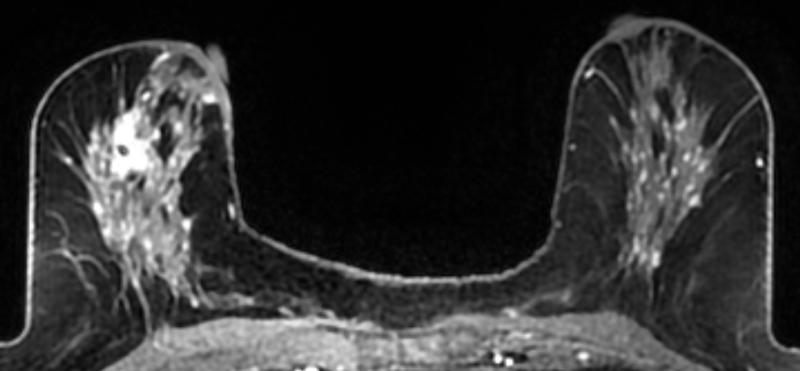

A 59-year-old female presented with a 3 cm palpable mass in the right breast. No identifiable abnormalities were identified on either the RMLO (on right) or RCC (on left) tomosynthesis images. (Image courtesy of Marc F. Inciardi, M.D., University of Kansas Medical Center)